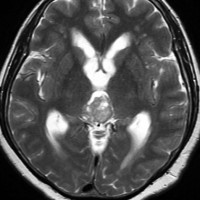

成人女性の松果体細胞腫で充実性腫瘍です。中脳水道が閉塞して軽度の水頭症(頭の中に髄液が溜まる)になってきています。多少凹凸がありますがだいたい楕円形。